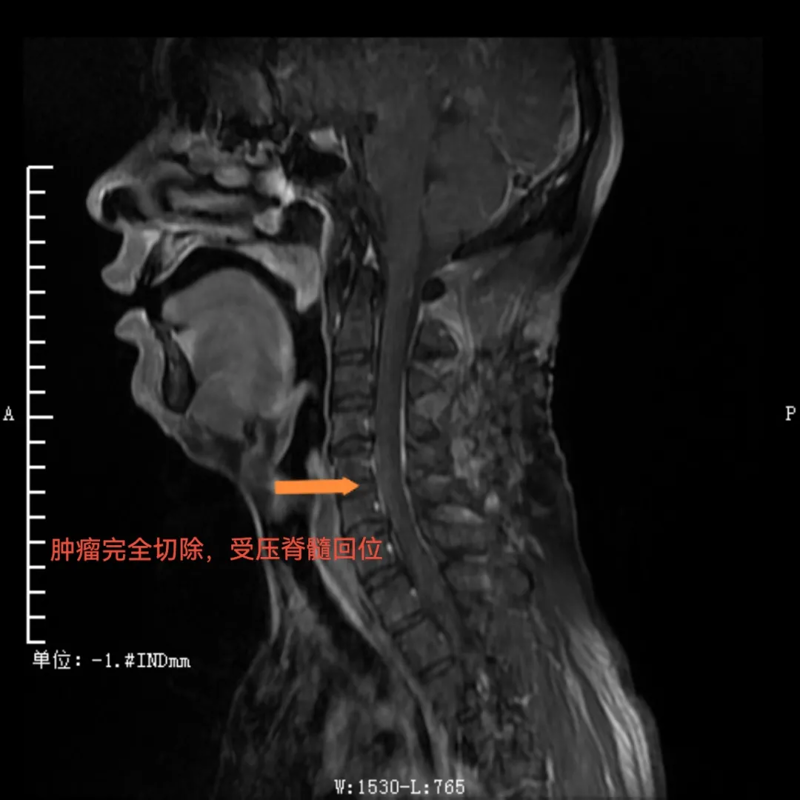

手术过程中,先由脊柱外科团队采取“单开门”的方式打开经4、5节段左侧椎板并向右侧掀起。这种独特的操作方式能够充分暴露肿瘤区域,再由神经外科团队在显微镜下打开硬脊膜并完整切除肿瘤。手术顺利,如今患者已出院,本人及家属对手术效果相当满意,赠送锦旗表示感谢。

术后,肿瘤完全切除,受压脊髓回位

与传统手术需要完全切除肿瘤节段全椎板不同,这种新的手术方式术后仅需将掀起的椎板纳还并以丝线固定即可,无需使用金属连接耗材固定。这不仅使得复位效果更佳,而且患者在术后复查CT、磁共振时无金属伪影干扰,让检查结果诊断更准确,还为患者节省了相当大的一笔费用。